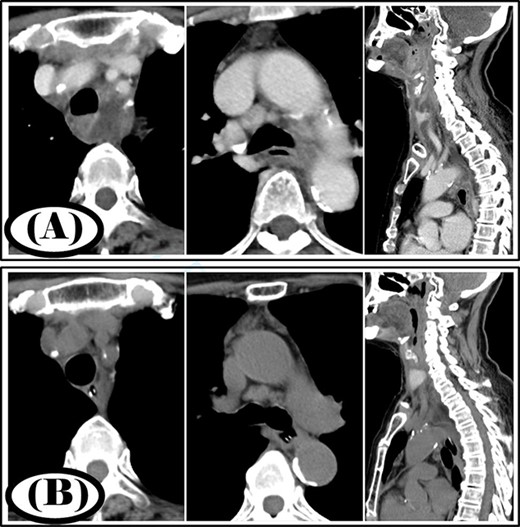

A 77-year-old woman had a chief complaint of sore throat and was diagnosed with a retropharyngeal abscess. Cervicothoracic computed tomography (CT) showed that the infection had spread to the mediastinum (Fig. 1A). The patient was diagnosed with type IIB DNM. Cervical drainage and mediastinal drainage through the cervical approach were performed on the day of admission. Staphylococcus epidermidis, Streptococcus mitis and Acinetobacter lwoffii were detected in the mediastinal abscess cavity. The patient was administered ampicillin/sulbactam at 12 g/day for 3 weeks. Continuous irrigation with saline (2 l/day) was initiated immediately post-surgery. The duration of irrigation, drainage and hospital stay were 4, 10 and 30 days, respectively. Four weeks post-surgery, cervicothoracic CT showed no abscess cavity and the infection had improved (Fig. 1B).

Case 1: pre- and post-treatment cervicothoracic CT; (A) pre-operative cervicothoracic CT and (B) cervicothoracic CT 4 weeks after treatment.